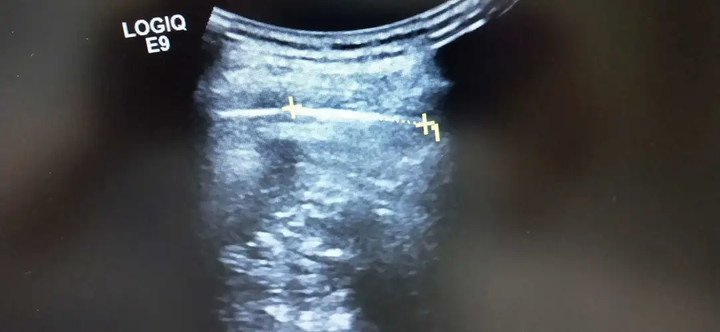

就這麼過了45年後,陳先生於今年5月胸部開始出現間斷性疼痛,越來越難以忍受,於是他在家人的陪同下前往浙江醫院三墩院區,胸部CT驚見異物,其中最長的10幾厘米,而且距離陳先生的脾臟只有3.2厘米。

經過對比確認,浙江醫院胸外科主任陳國平主任醫師表示,陳先生體內的異物確定是兩塊玻璃,有感染跡象,而且還刺激到周圍組織,導致難以承受的疼痛。

「玻璃卡在肋間,跟脾臟隔了一層薄薄的膈肌,有可能刺破脾臟,也有可能割破肋間的動靜脈,這會導致大出血,危及生命。」陳國平建議,陳先生進行抗感染治療後,立即進行手術,取出玻璃塊。